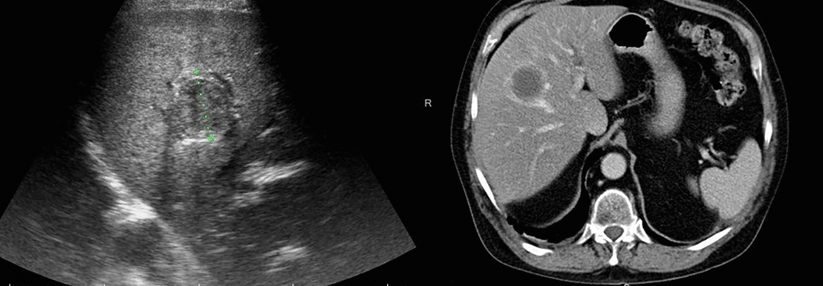

Schwellungen im Gesicht habe er seit seiner Reise immer wieder mal. Im Ultraschall sehen die Ärzte eine unter der Haut liegende, linsenförmige Struktur mit faden- und schnurförmigen Einschlüssen. Eine nachfolgende MRT bestätigt den Befund. Der Patient wird operiert und ein etwa 1 cm großer Tumor entfernt. In der Histologie zeigen sich Anschnitte eines schwangeren Wurms. In der anschließenden Blutuntersuchung mittels Dickem Tropfen ist eine Mikrofilarie zu erkennen. Die Morphologie entspricht der von Dilofilaria repens, dem Hundehautwurm.